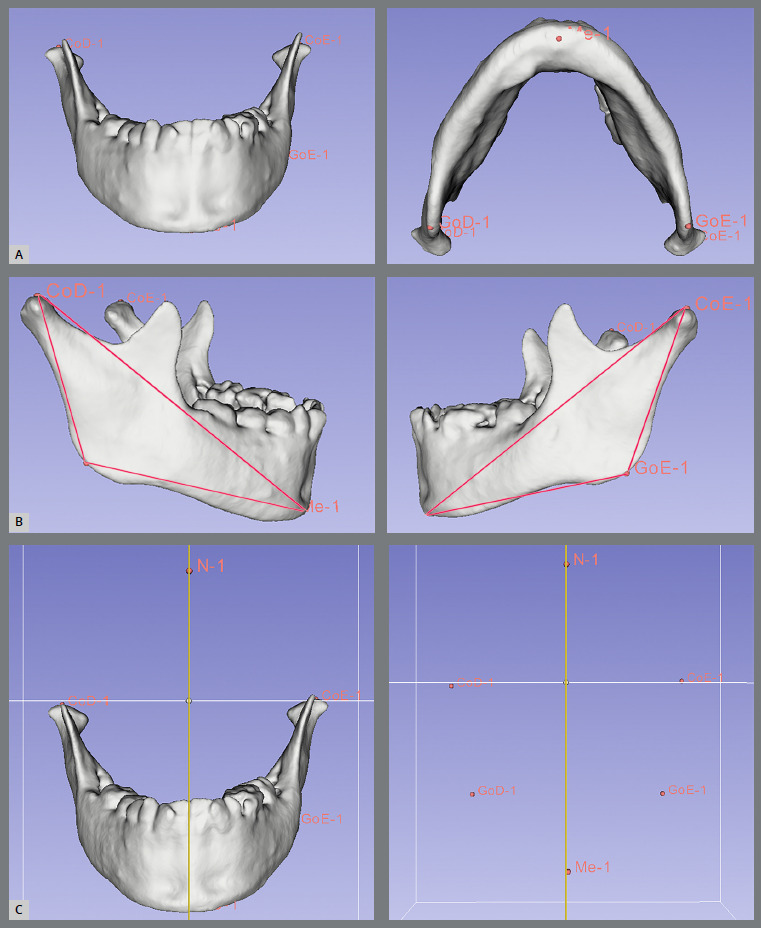

Methods: Cone-beam computed tomography (CBCT) of 47 UCLP patients were included, and divided into two groups (prepubertal stage and pubertal stage). The mandibular ramus height (Co-Go), mandibular body length (Go-Me), total mandibular length (Co-Me), gonial angle (CoGoMe), the volume of the mandibular condyles, and lateral chin deviation were evaluated. The cleft side (CS) and noncleft side (NCS) were compared using the paired t-test for dependent samples. Chin deviation and its possible association with specific sides were evaluated using the Mann-Whitney and Fisher's Exact tests, respectively. The significance level was set at 5%.